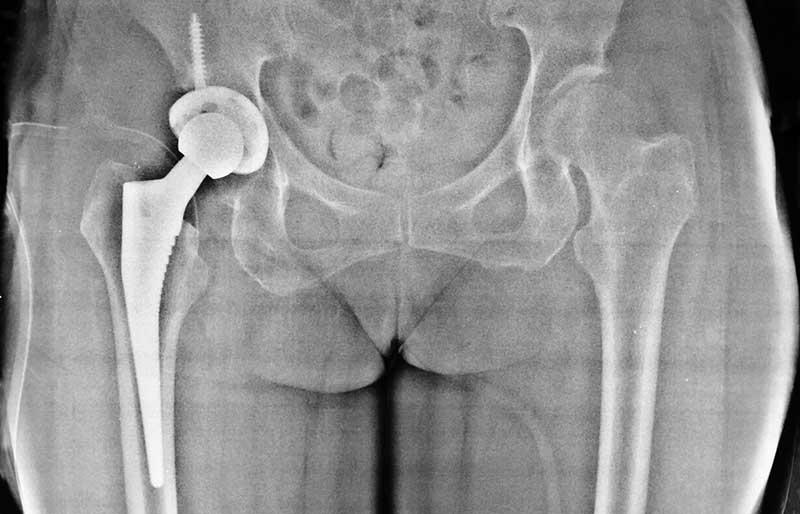

Operasi penggantian sendi panggul adalah suatu operasi untuk mengganti sendi panggul yang rusak dengan sendi buatan yang disebut prosthesis. Penyebab utama kerusakan sendi panggul adalah osteoartritis (baca penjelasan tentang “Osteoartritis”) dan sendi panggul adalah sendi terbanyak kedua setelah lutut yang terserang penyakit ini.

Operasi penggantian sendi panggul merupakan pengobatan terbaik untuk osteoartritis panggul stadium yang berat. Ada empat tujuan operasi ini, yaitu menghilangkan rasa sakit sendi yang telah rusak, memperbaiki lingkup gerak sendi yang sebelumnya kaku dan terbatas, mengembalikan kemampuan penderita melakukan aktivitas harian tanpa rasa sakit, dan meningkatkan kualitas hidup sehingga penderita kerusakan sendi dapat menjalani hidup secara aktif bebas dari nyeri sendi panggul.